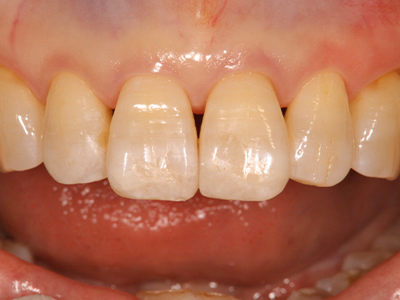

前歯のセラミックス

治療前後写真

治療前

治療後

50歳・女性

前歯の変色・審美障害

全体ホワイトニング→失活歯(#11)を再根管治療→#11フルセラミックス修復

#21はレジン充填

治療期間

約3ヶ月

- ホワイトニング 88,000円

- 感染根管治療 121,000円

- セラミック 170,500円

- コンポジットレジン 33,000円

歯肉退縮で境目が見える可能性

過度な咬合力でセラミックのチッピング

医院コメント

生物学的安定性を確保した上でセラミックを接着し、色・透明感を自然に調和。